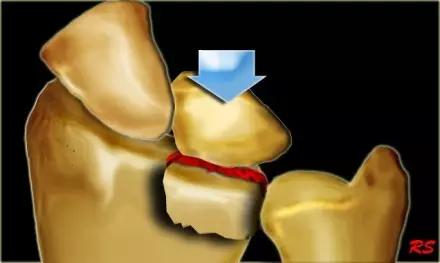

4. Die-punch 骨折

远端桡骨的关节内骨折,伴有月骨陷窝背侧表面的压迫。也称月骨负荷骨折或模具冲压骨折,指挠骨的月骨对应面发生的向近侧的压缩骨折,有不与周围关节囊相连的游离关节面骨折块。

Die-punch 骨折(来源:radiology assistant)